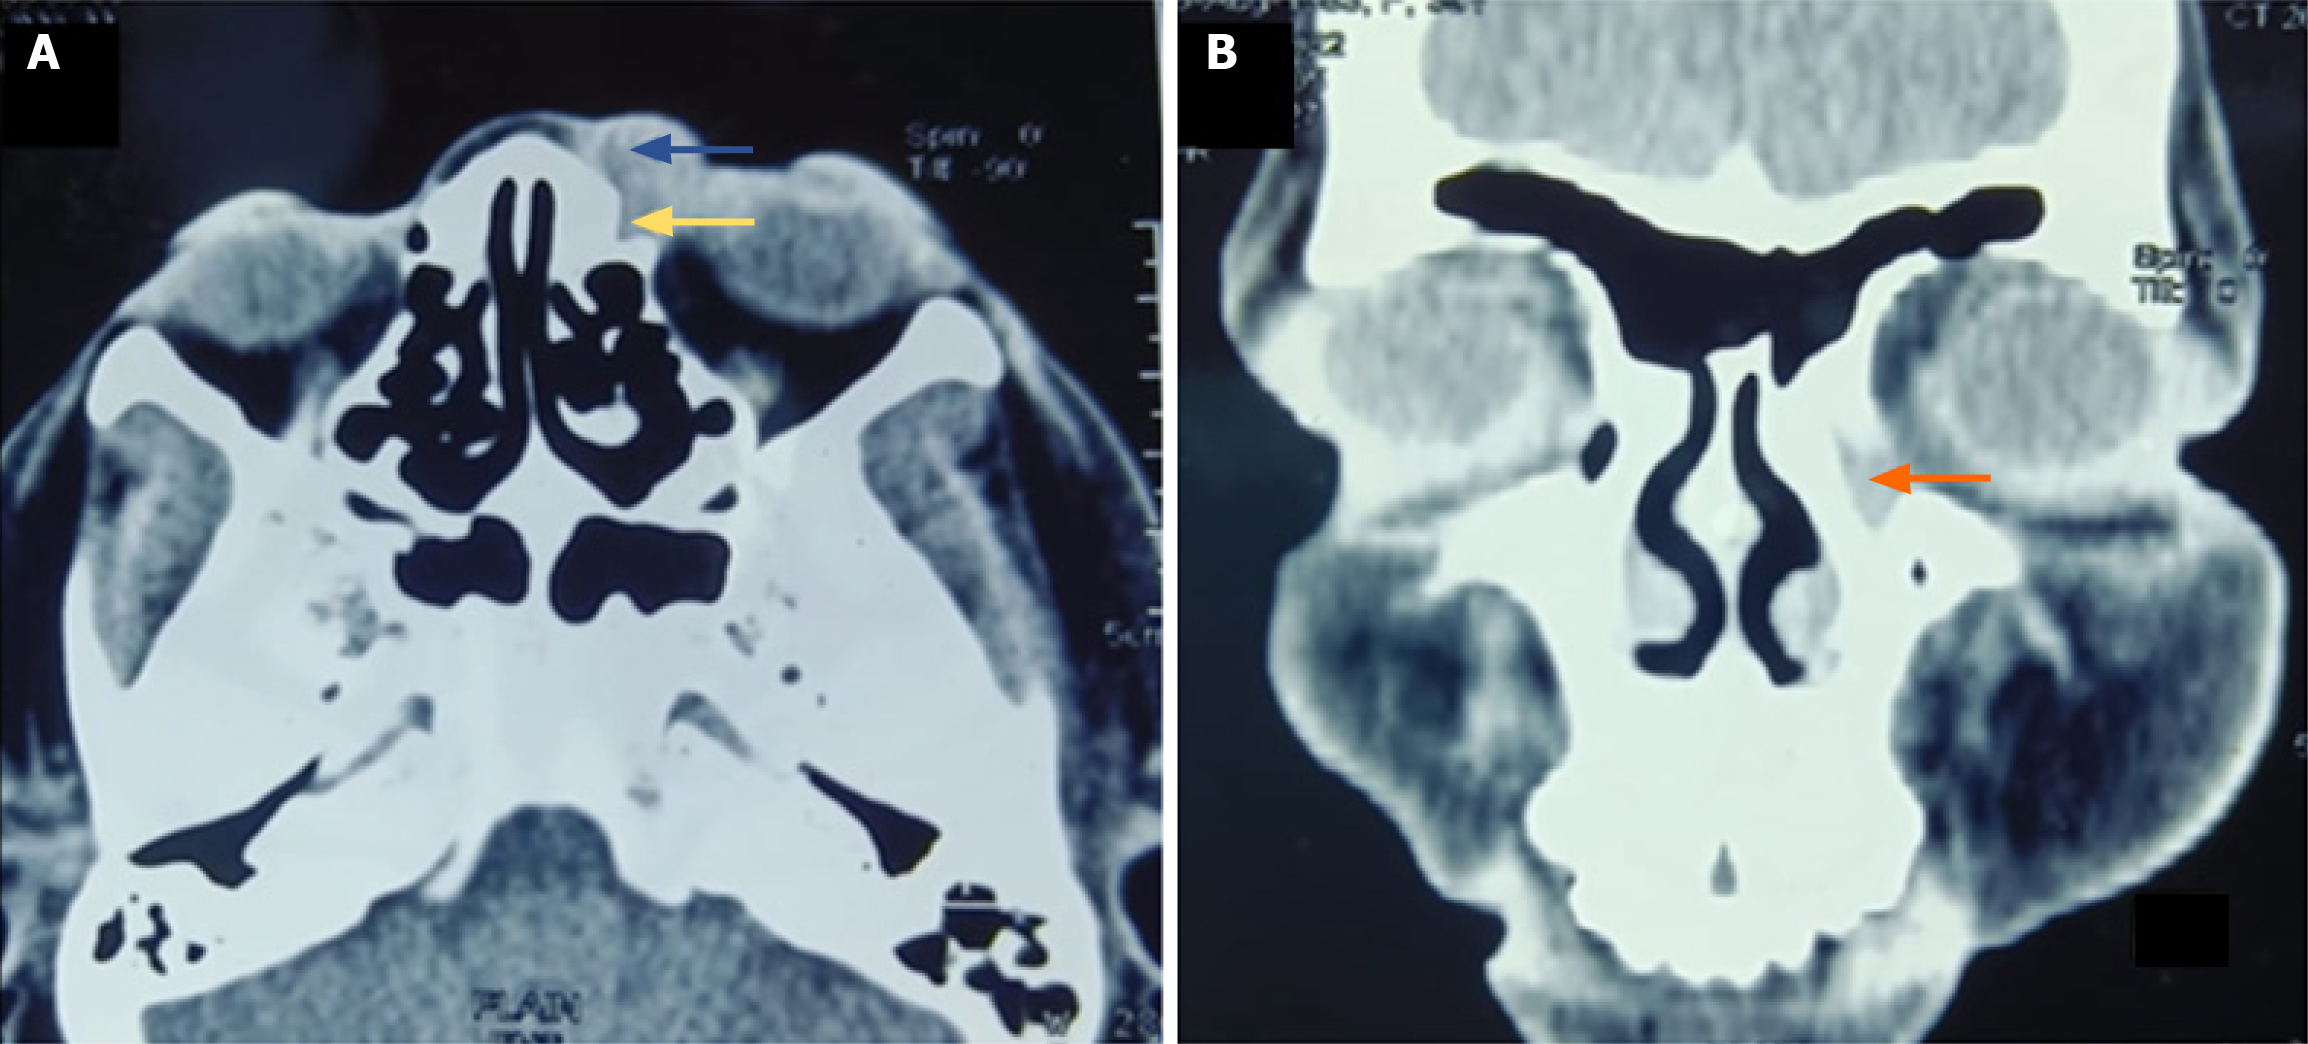

Figure 3 Computed tomography.

A and B: Isodense mass lesion in lacrimal sac area showing extension into preseptal area (marked with yellow arrow), left nasolacrimal duct (marked with orange arrow).